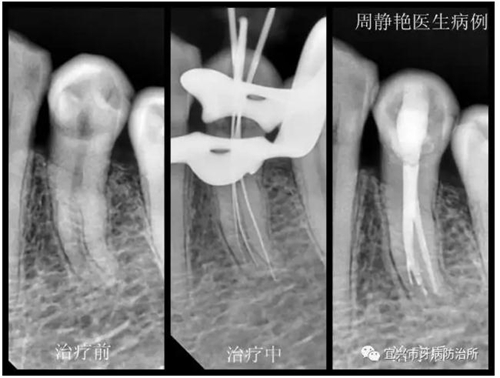

患者鄭女士,61歲,一個月以來,左下后牙經(jīng)常冷熱刺激痛,一周來疼痛加劇,夜間痛明顯,冷刺激更甚。經(jīng)X光檢查,34根尖無明顯陰影,根管形態(tài)復雜,疑是根中分為雙根管或C形根管。上障,34局麻下去腐,開髓,拔髓,根管探查,疑是3根管,拍診斷絲片。再次根管蕩洗,熱牙膠充填,流動樹脂墊底,樹脂充填。囑一月后復查,冠修復。